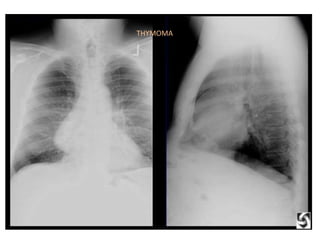

THYMOMA

• thymoma

• The fourT's make up the mnemonic for anterior mediastinal masses: • Thymoma (myasthenia, upper anterior mediatinum) • Teratoma (germ cell) • Thyroid • Terrible Lymphoma

• 125.

• 126.